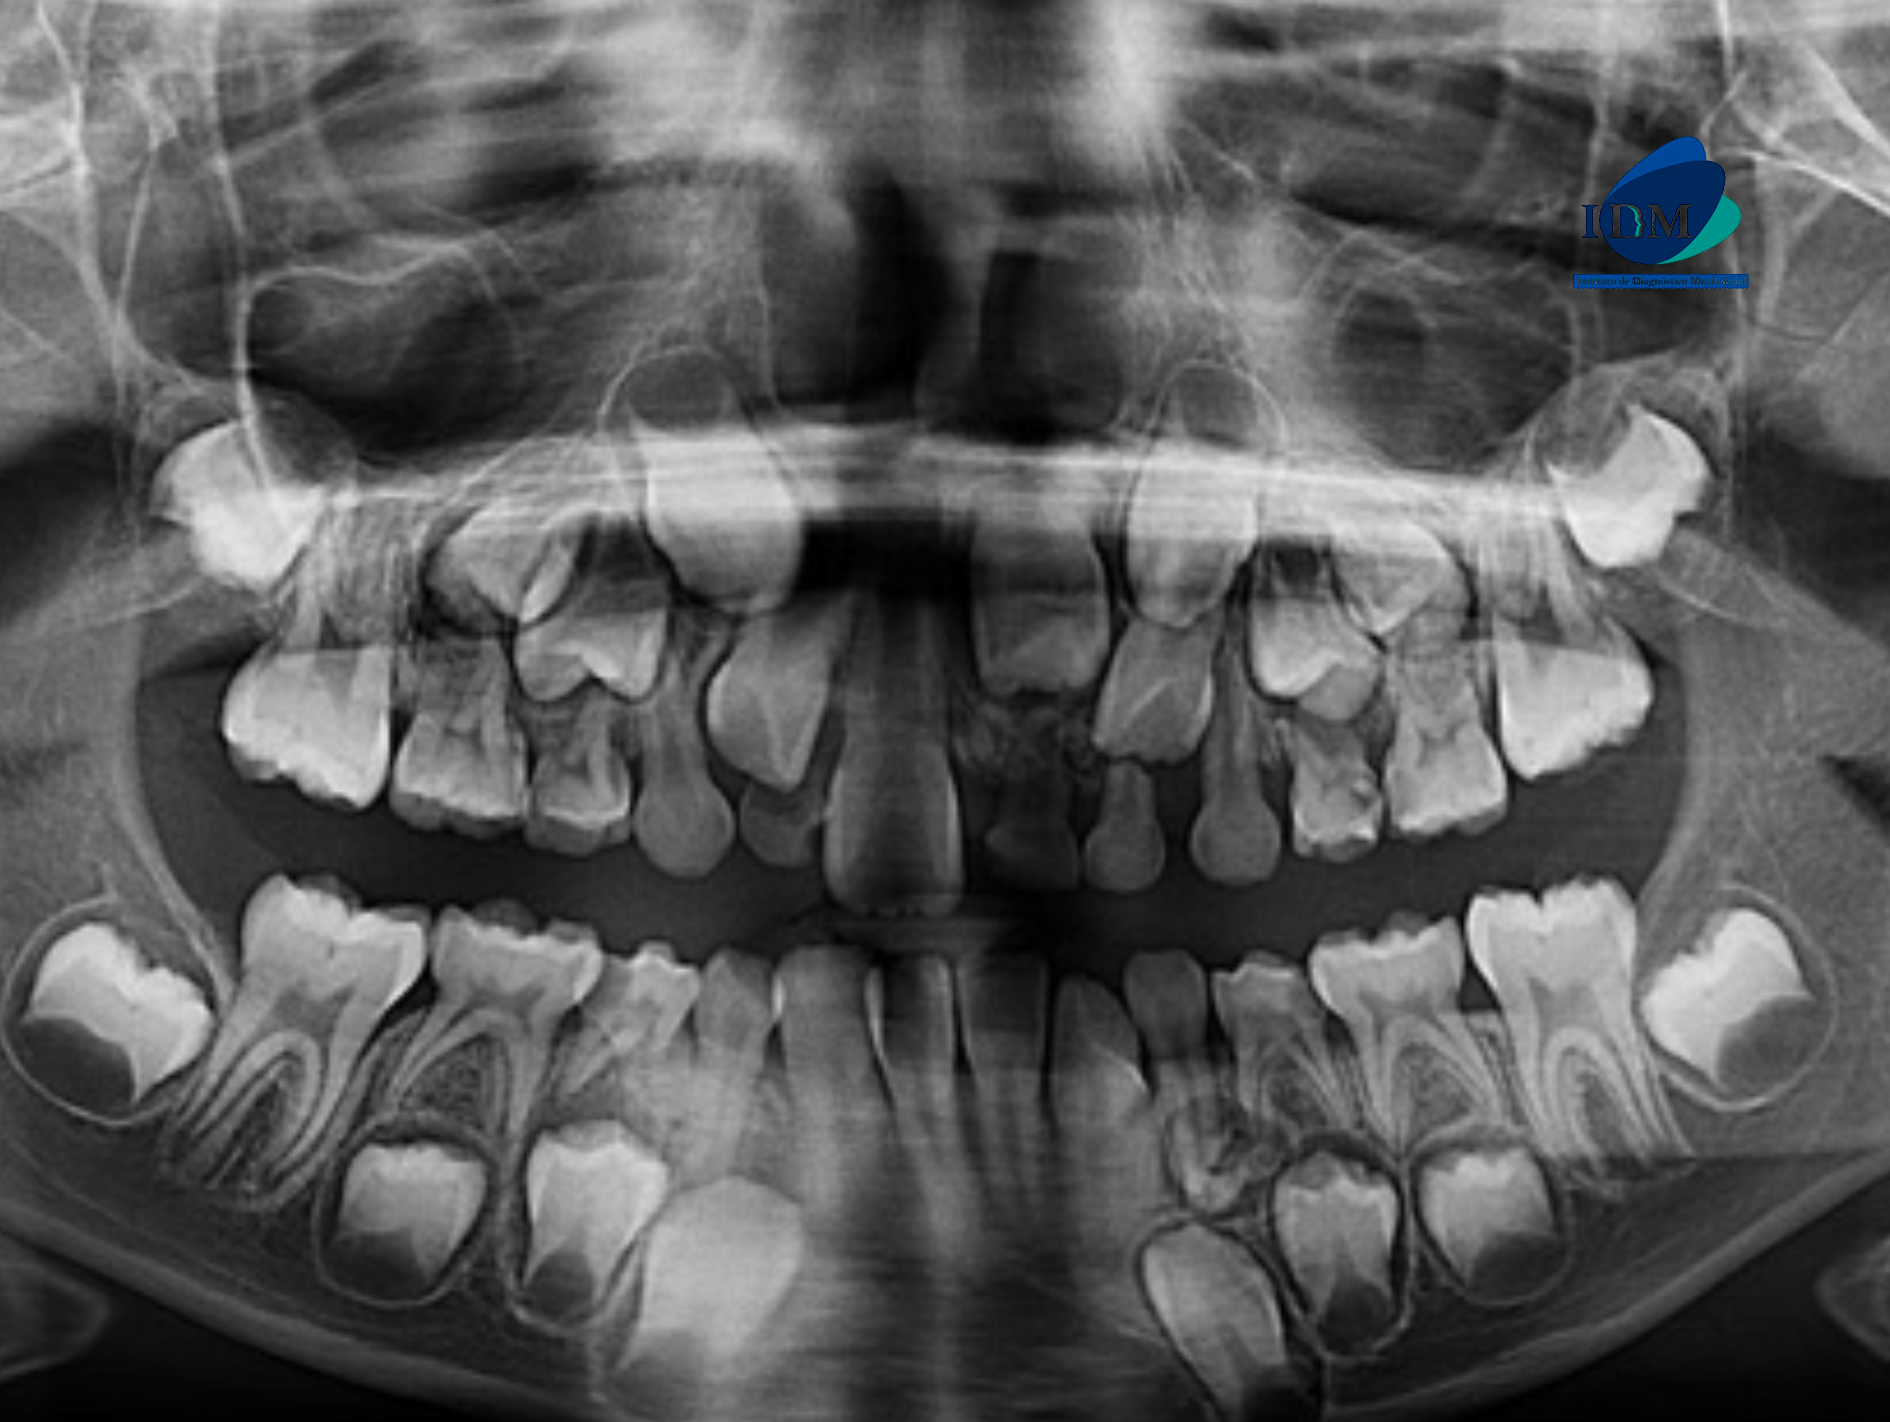

Paciente masculino de 08 años de edad, es referido al Instituto de Diagnóstico Maxilofacial – IDM para evaluación general.

En la radiografía panorámica (Figura 1), se aprecia imagen radiopaca circunscrita con un halo radiolúcido proyectado sobre el tercio medio radicular de pieza 61 y tercio apical de pieza 73.

Radiografia Panorámica